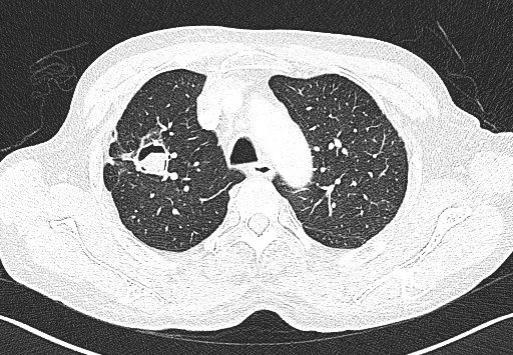

但在少数情况下,身体抵抗力好,长期居住在潮湿发霉环境下,也可能感染霉菌。典型的霉菌感染,会在肺部形成曲霉球。

图1:曲霉球